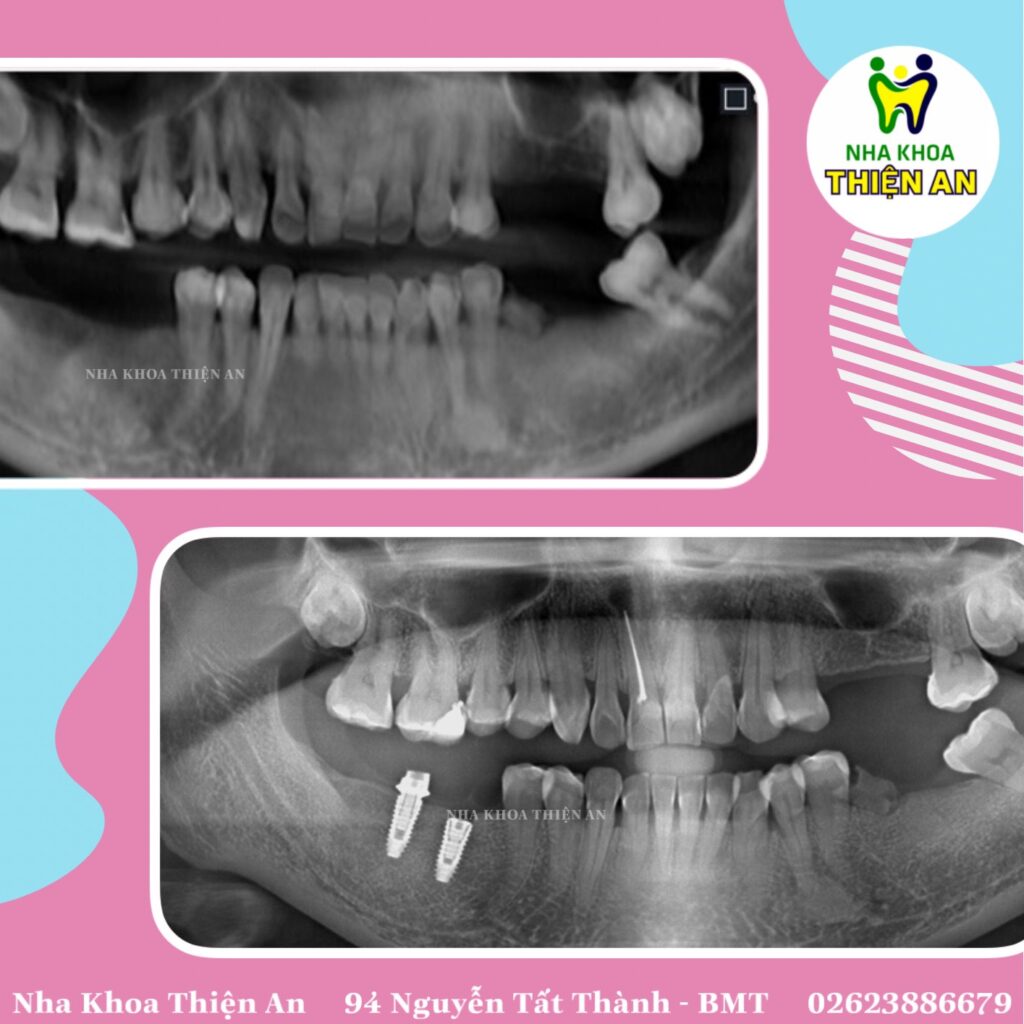

Ứng dụng kĩ thuật số vào implant cho các quý khách hàng thân yêu tại nha khoa Thiện An BMT – Đăk Lăk. Hiện nay, toàn bộ quy trình cấy ghép implant cho đến làm răng sứ, nha khoa Thiện An BMT – Đăk Lăk đều ứng dụng kĩ thuật số từ chẩn đoán, ra kế hoạch điều trị, thực hiện và làm phục hình răng sứ trên implant với mong muốn đem lại trải nghiệm tốt nhất cho quý khách hàng

Digital application to implants for dear customers at Thien An BMT Dental Clinic – Dak Lak. Currently, the entire process of implant implantation to making porcelain teeth, Thien An BMT dentistry – Dak Lak uses digital applications from diagnosis, treatment planning, implementation and restoration of porcelain teeth on implants. With the desire to bring the best experience to our customers ❤️❤️